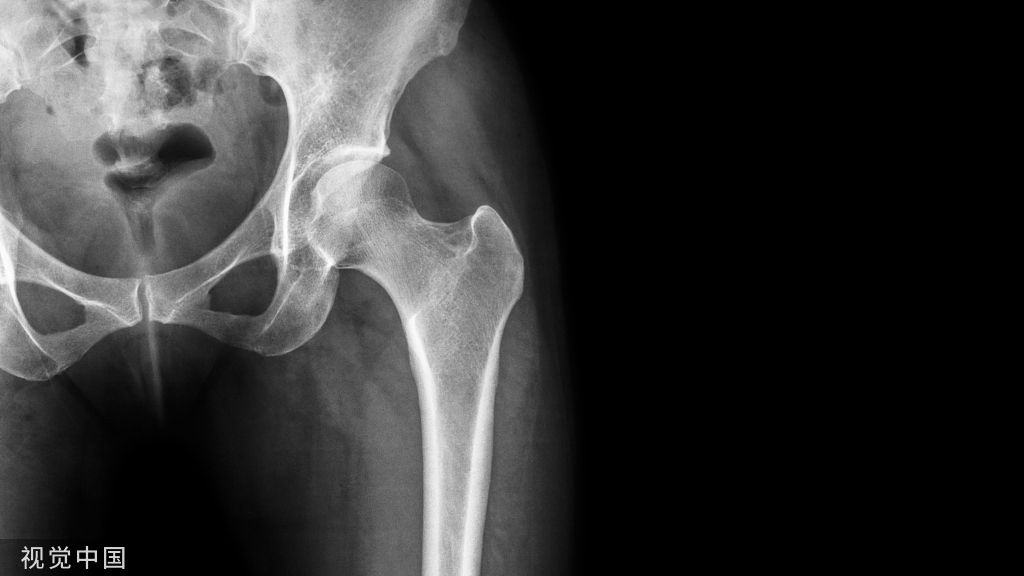

技术要点股骨髁骨板,重点在髁部,故髁部切口较长,利用该切口取出远端螺钉及折断的远端接骨板;通过克氏针的引导,于近端复加数个小切口经皮取出相应的螺钉,于远端切口取出折断的近端接骨板。

注意事项小切口取接骨板切口设计固然重要但适应证更为重要。如果接骨板表面骨质较多,螺孔滑丝或螺钉断裂,接骨板外有其他金属固定物,骨折继发膝关节强直需行股四头肌松解,应根据具体情况扩大切口,开放或延长原切口,甚至另做新切口。本病例由于股骨骨不连造成接骨板折断,需要清理骨折断端并植骨,所以远端切口适当延长。